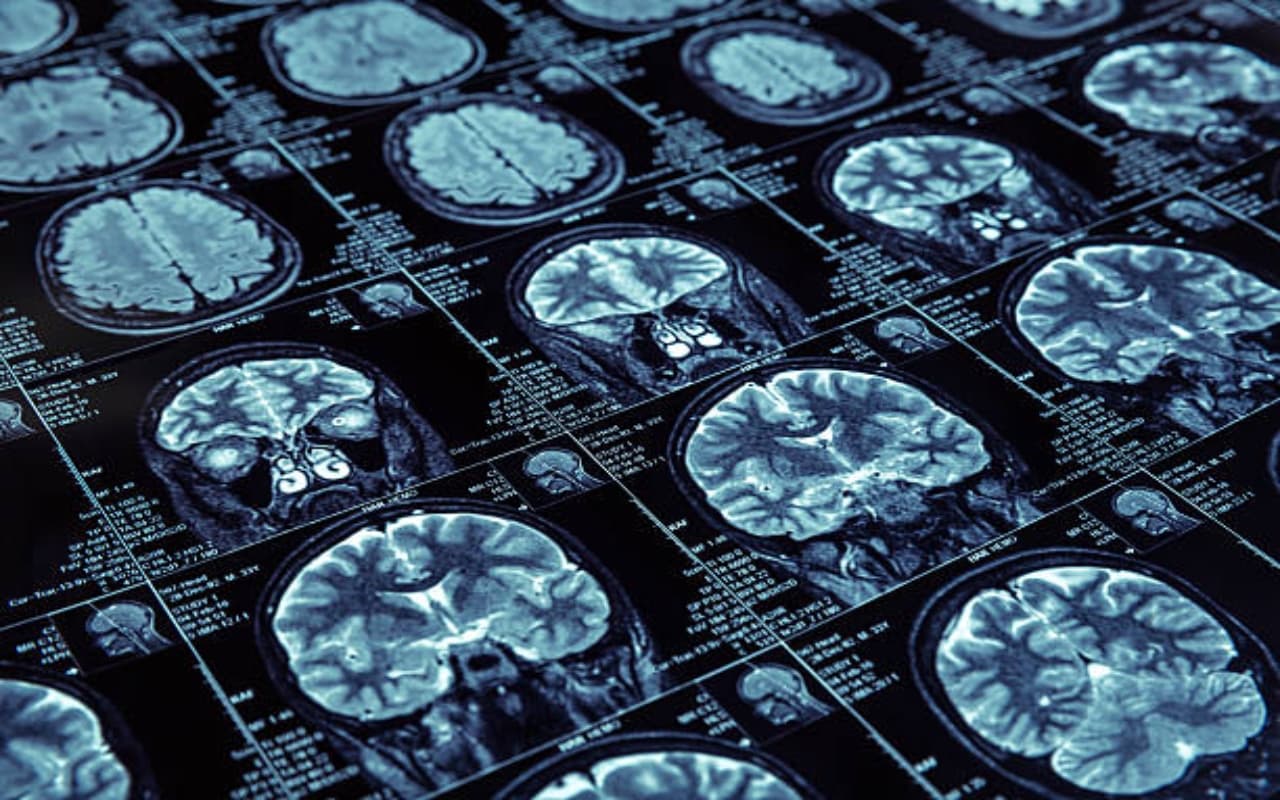

चुंबकीय अनुनाद इमेजिंग, Magnetic resonance imaging (MRI) जांच का एक तरीका है, जहां एक्स-रे या सीटी स्कैन के विपरीत, चुंबकीय क्षेत्र और रेडियो तरंगों (विकिरण नहीं) का उपयोग किया जाता है. एमआरआई उपकरण एक शक्तिशाली चुंबकीय क्षेत्र बनाता है . इसके कारण, मानव शरीर में प्रोटॉन इस क्षेत्र के अनुसार पंक्तिबद्ध हो जाते हैं फिर स्कैनर रेडियो तरंगों की एक पल्स उत्सर्जित करता है, जो प्रोटॉन को लाइन से बाहर कर देता है जब प्रोटॉन अपनी मूल स्थिति में लौटते हैं, तो वे ऊर्जा छोड़ते हैं जिसे सिग्नल कहा जाता है इन संकेतों को रिकॉर्ड किया जाता है, उनका विश्लेषण किया जाता है और शरीर के आंतरिक हिस्सों की विस्तृत छवियां बनाने के लिए उपयोग किया जाता है. जब अंगों या कोमल ऊतकों की जांच करनी हो तो सीटी के बजाय एमआरआई का उपयोग किया जा सकता है. एमआरआई सॉफ्ट टिशू के प्रकारों के बीच अंतर देखने और यह निर्धारित करने में मदद करता है कि कौन से स्वस्थ हैं और कौन से नहीं.